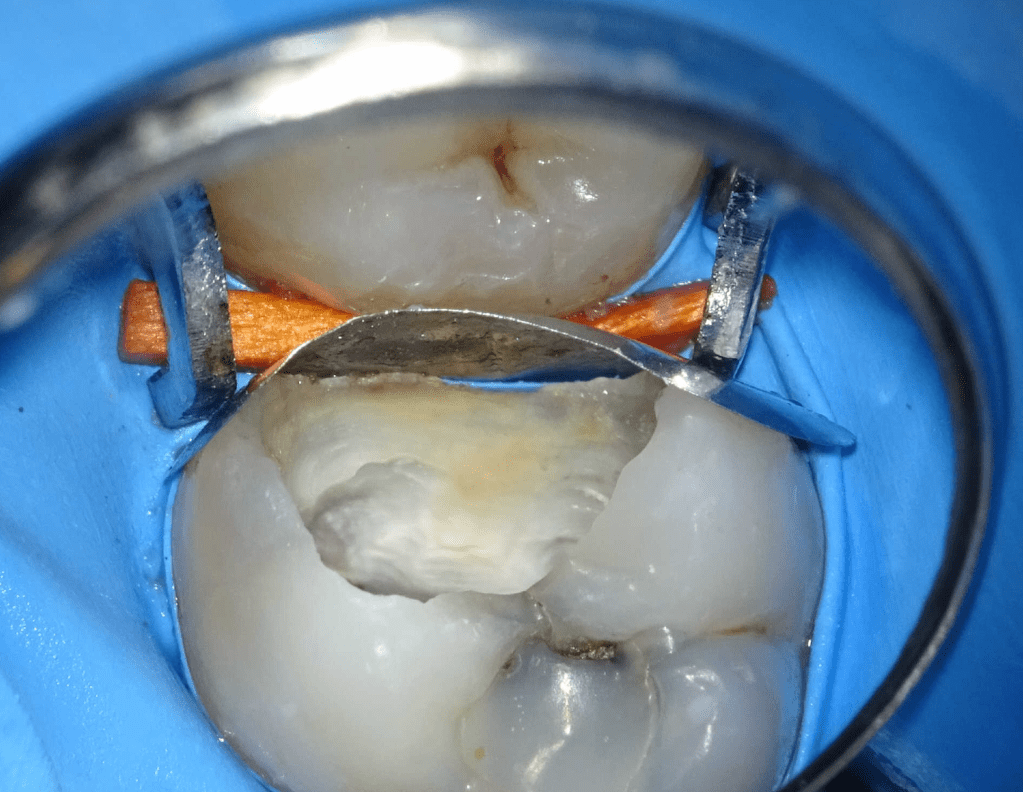

Reconstrucción preendodóntica

Reco pared vesticular